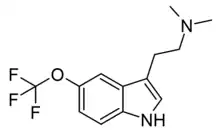

| 5-TFMO-DMT[12] | artificial | 5-OCF3 | CH3 | CH3 | 5-(trifluoromethoxy)-N,N-dimethyltryptamine | |